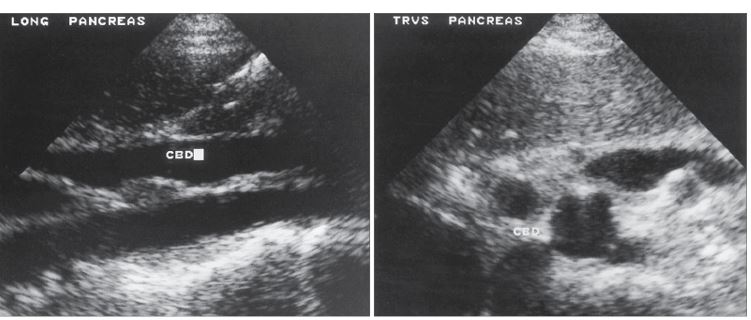

1. Portal Vein

2. Common Bile Duct

3. Gallbladder

CBD

arrow: CBD

curved arrow: CBD

Common Bile Duct doesn’t catch COLOR

SAG - CBD

Carcinoma of the head of the pancreas with obstruction of the common bile duct (CBD) is demonstrated